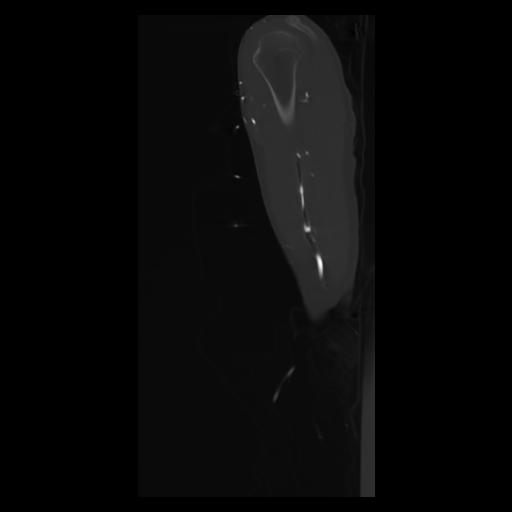

30 CUERPO,CE,Sagittal,3.000,CUERPO,Sagittal,